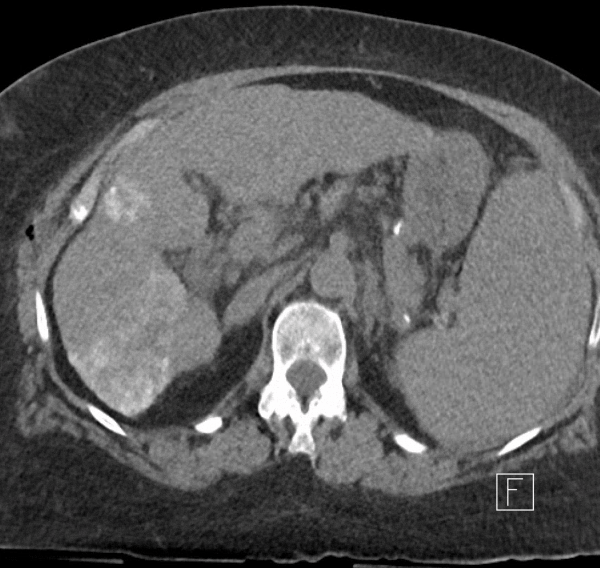

Transarterial Chemoembolisation (TACE)

Spectrum IR offers Transarterial Chemoembolisation (TACE) as a targeted therapy for intermediate-stage hepatocellular carcinoma (HCC). This minimally invasive procedure delivers high-concentration chemotherapy drugs directly to liver tumors while simultaneously blocking their blood supply, effectively attacking cancer cells from multiple angles. Our interventional radiologists use advanced imaging to navigate through blood vessels with precision, sparing healthy liver tissue while maximising treatment effect on tumors. TACE can provide valuable disease control and extended survival for patients with intermediate HCC. This outpatient procedure typically allows patients to return home the same day with significantly less recovery time than traditional surgical approaches.

Selective Internal Radiation Therapy (SIRT)

Spectrum IR provides Selective Internal Radiation Therapy (SIRT) using SIRTEX resin microspheres for patients with challenging liver cancers. This advanced treatment delivers millions of radioactive yttrium-90 coated beads directly to liver tumours through their blood supply, precisely targeting cancer cells while minimising exposure to healthy tissue. SIRT offers an effective option for patients with large or late-stage hepatocellular carcinoma (HCC) and those with oligometastatic liver disease from colorectal and other primary tumours. Our interventional radiologists perform comprehensive mapping and planning before each procedure to ensure optimal delivery and safety. SIRT can provide meaningful tumour control and improved quality of life when other treatments may have limited effectiveness, making it a valuable addition to our comprehensive interventional oncology arsenal.